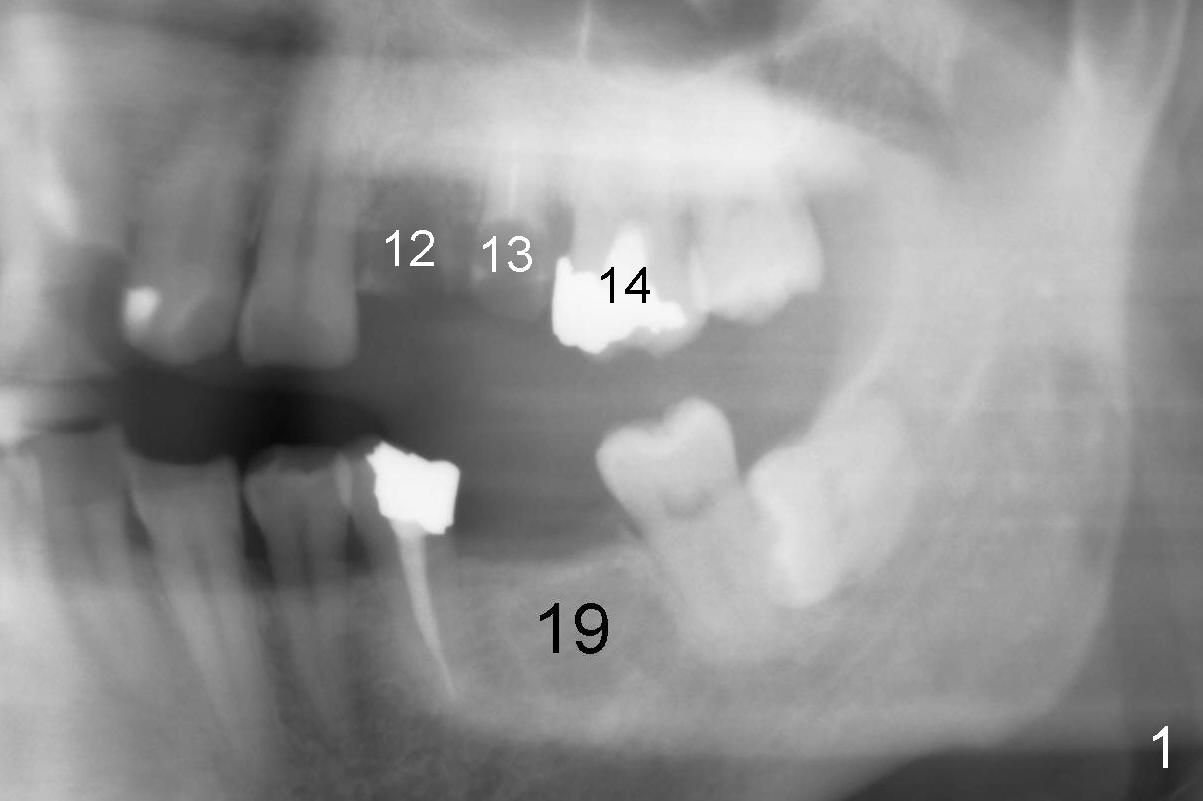

A 51-year-old man needs implants at the sites of #12,13,19 (Fig.1). The teeth #12 and 13 are extracted. An implant is placed at #19 (Fig.2 <). After osteointegration, an abutment is placed (Fig.2 A). The opposing tooth, #14, is found supraerupted. Two mini-implants are placed at the mesiobuccal and distolingual areas of #14 (Fig.3 (mirror view) <) and a power chain (*) is placed for intrusion. In the next 8 months, these 2 mini-implants become loose. Two new mini-implants are placed in the mesiolingual and distobuccal regions (Fig.4 ^). The one in the distobuccal region is loose after a while (Fig.6,7 >). In brief, mini-implants are not efficient in intrusion. At this time, the implants at the sites of #12,13 apparently osteointegrate (3 months post placement) and abutments are placed (Fig.4). Provisional crowns are fabricated (Fig.5). Brackets are placed between #11 and 15 with the bracket at #14 placed more coronally than those of the neighboring teeth (Fig.6-8). Mesially there are two excellent anchorages (#12,13) as well as the mesiolingual mini-implant. The distal anchorage is #15. In the next 5.5 months, the tooth #14 is intruded (Fig.9,10), but the 2nd molar is mobile (not as strong as #14). A longer mini-implant is placed in the distobuccal corner (>, more apical than before (Fig.7)). The distobuccal mini-implant is found to be mobile in 3 weeks (Fig.11). It appears that there is enough clearance for restoration of #19 (Fig.12). Power chains are placed between the mesiolingual mini-implant and #14 buccal tube until the appointment for crown prep. In this way, the lingual cusps may ascend (Fig.13 red arrow), while the buccal ones may descend (black arrow). The occlusal clearance will be more favorable.